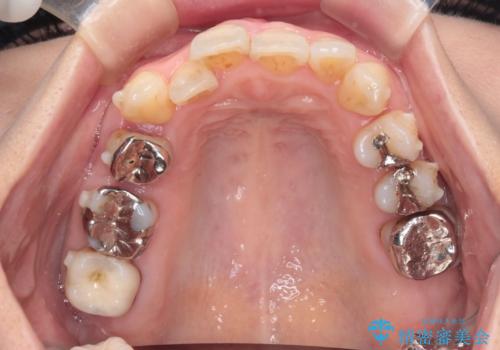

今回の治療では、右上5番の抜歯スペースを活用して八重歯(3番)を後方へ誘導しました。

インビザライン独自の3Dシミュレーションに基づき、必要な歯だけをピンポイントで動かすことで、抜歯を伴う大きな移動も効率的に行いました。

治療の結果、突出していた八重歯はきれいなアーチに収まり、左右対称でバランスの取れた口元になりました。インビザラインは自由に取り外しができるため、治療期間中も口腔内を清潔に保ちやすく、患者様もストレスなく治療を完了されました。